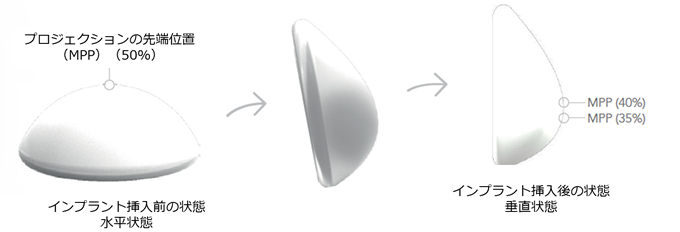

そして、最大の特徴は寝ている状態でも起きている状態でも自然で美しいバストをキープできることです。

これは、重力にともない頂点(バッグの重心)が動く仕組みになっているからです。